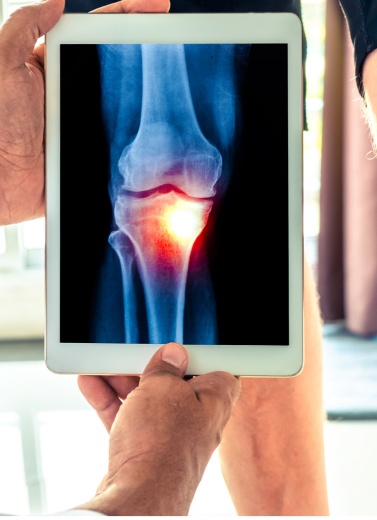

Arthritis and rheumatologic diseases can severely aect your quality of life with persistent pain, swelling, and limited movement. At our Rheumatology & Arthritis Department, Dr. Anand Bhushan oers comprehensive diagnosis and tailored treatments that control symptoms, slow disease progression, and improve joint function.

Osteoarthritis (Wear-and-Tear Arthritis)